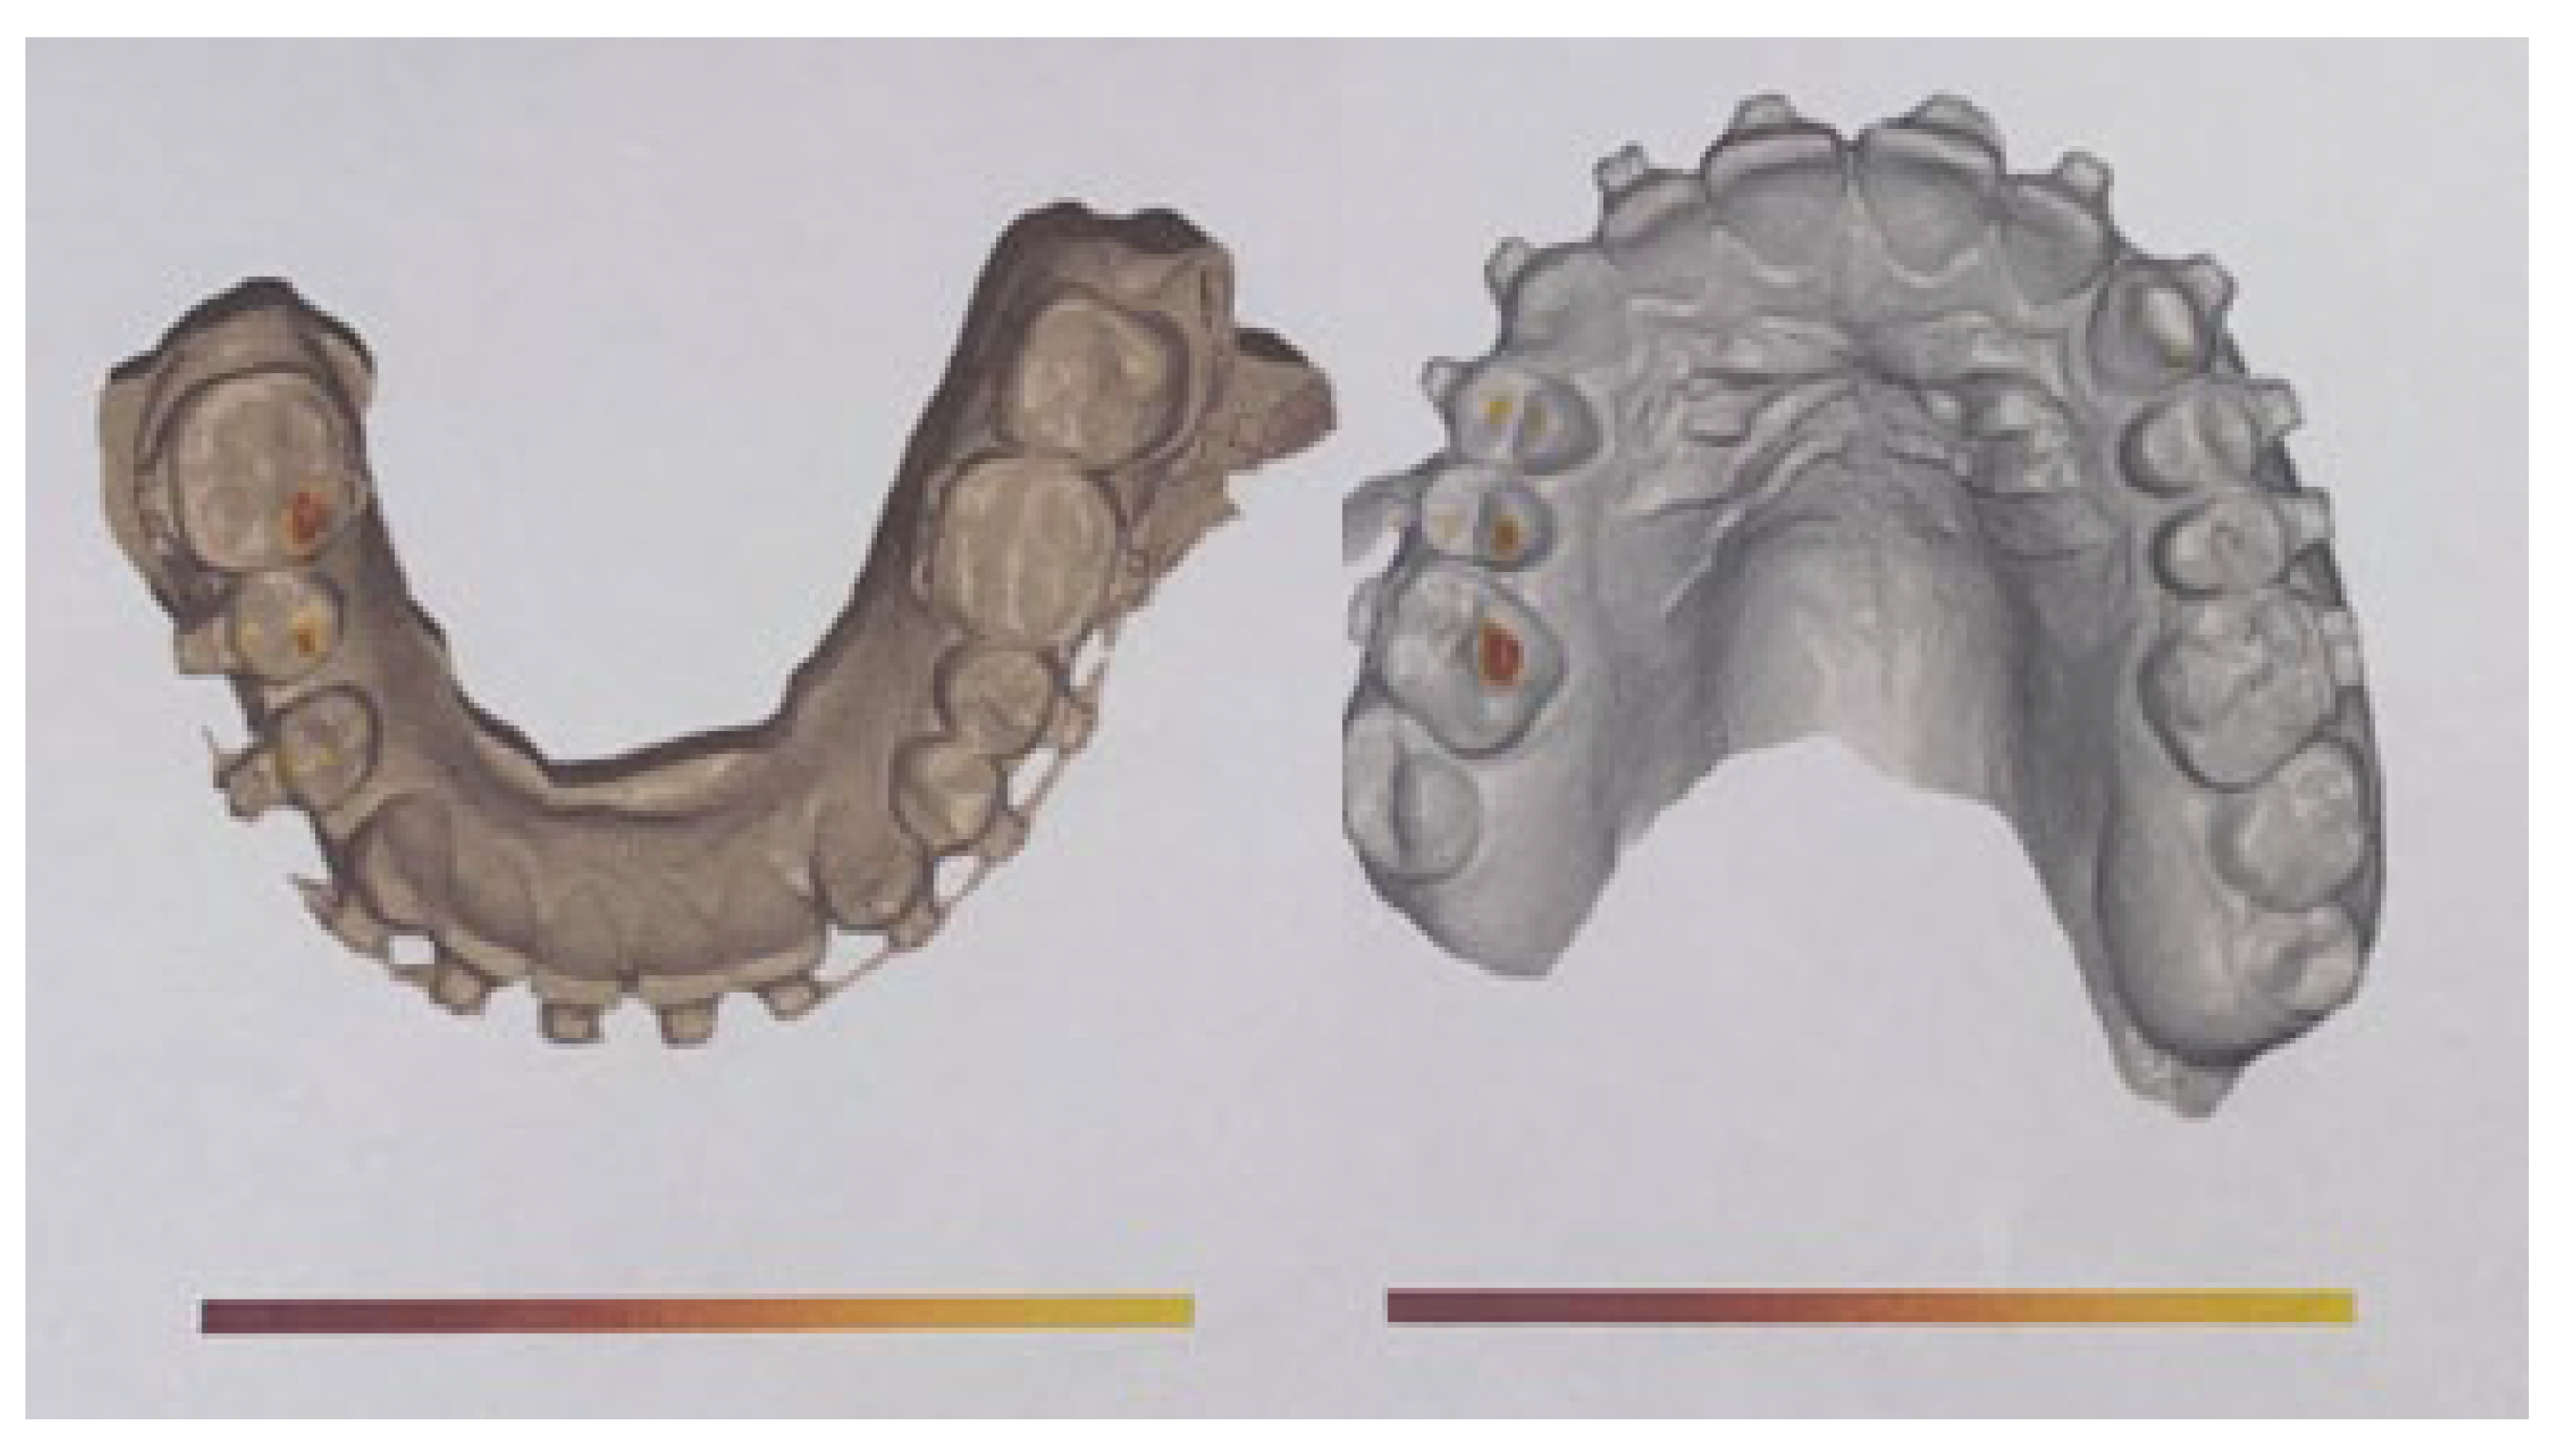

5. Imaging Tests for Diagnosis